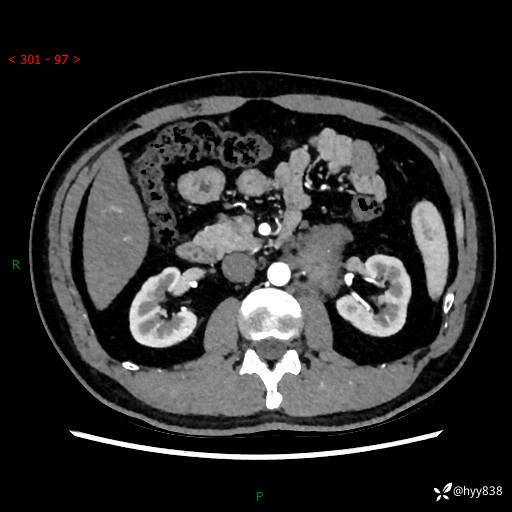

现病史:患者3月余前检查发现左侧腹膜后占位,大小约3.7*4.9cm,平素无腰疼,无肉眼血尿,无尿频尿急等不适,当时未特殊处理,在门诊复查CT提示左侧腹膜后占位,门诊拟“左侧腹膜后占位”收入院。 起病以来,患者精神佳,饮食、睡眠良好,大小便正常,体力体重无明显变化。

腹膜后CT平扫+增强